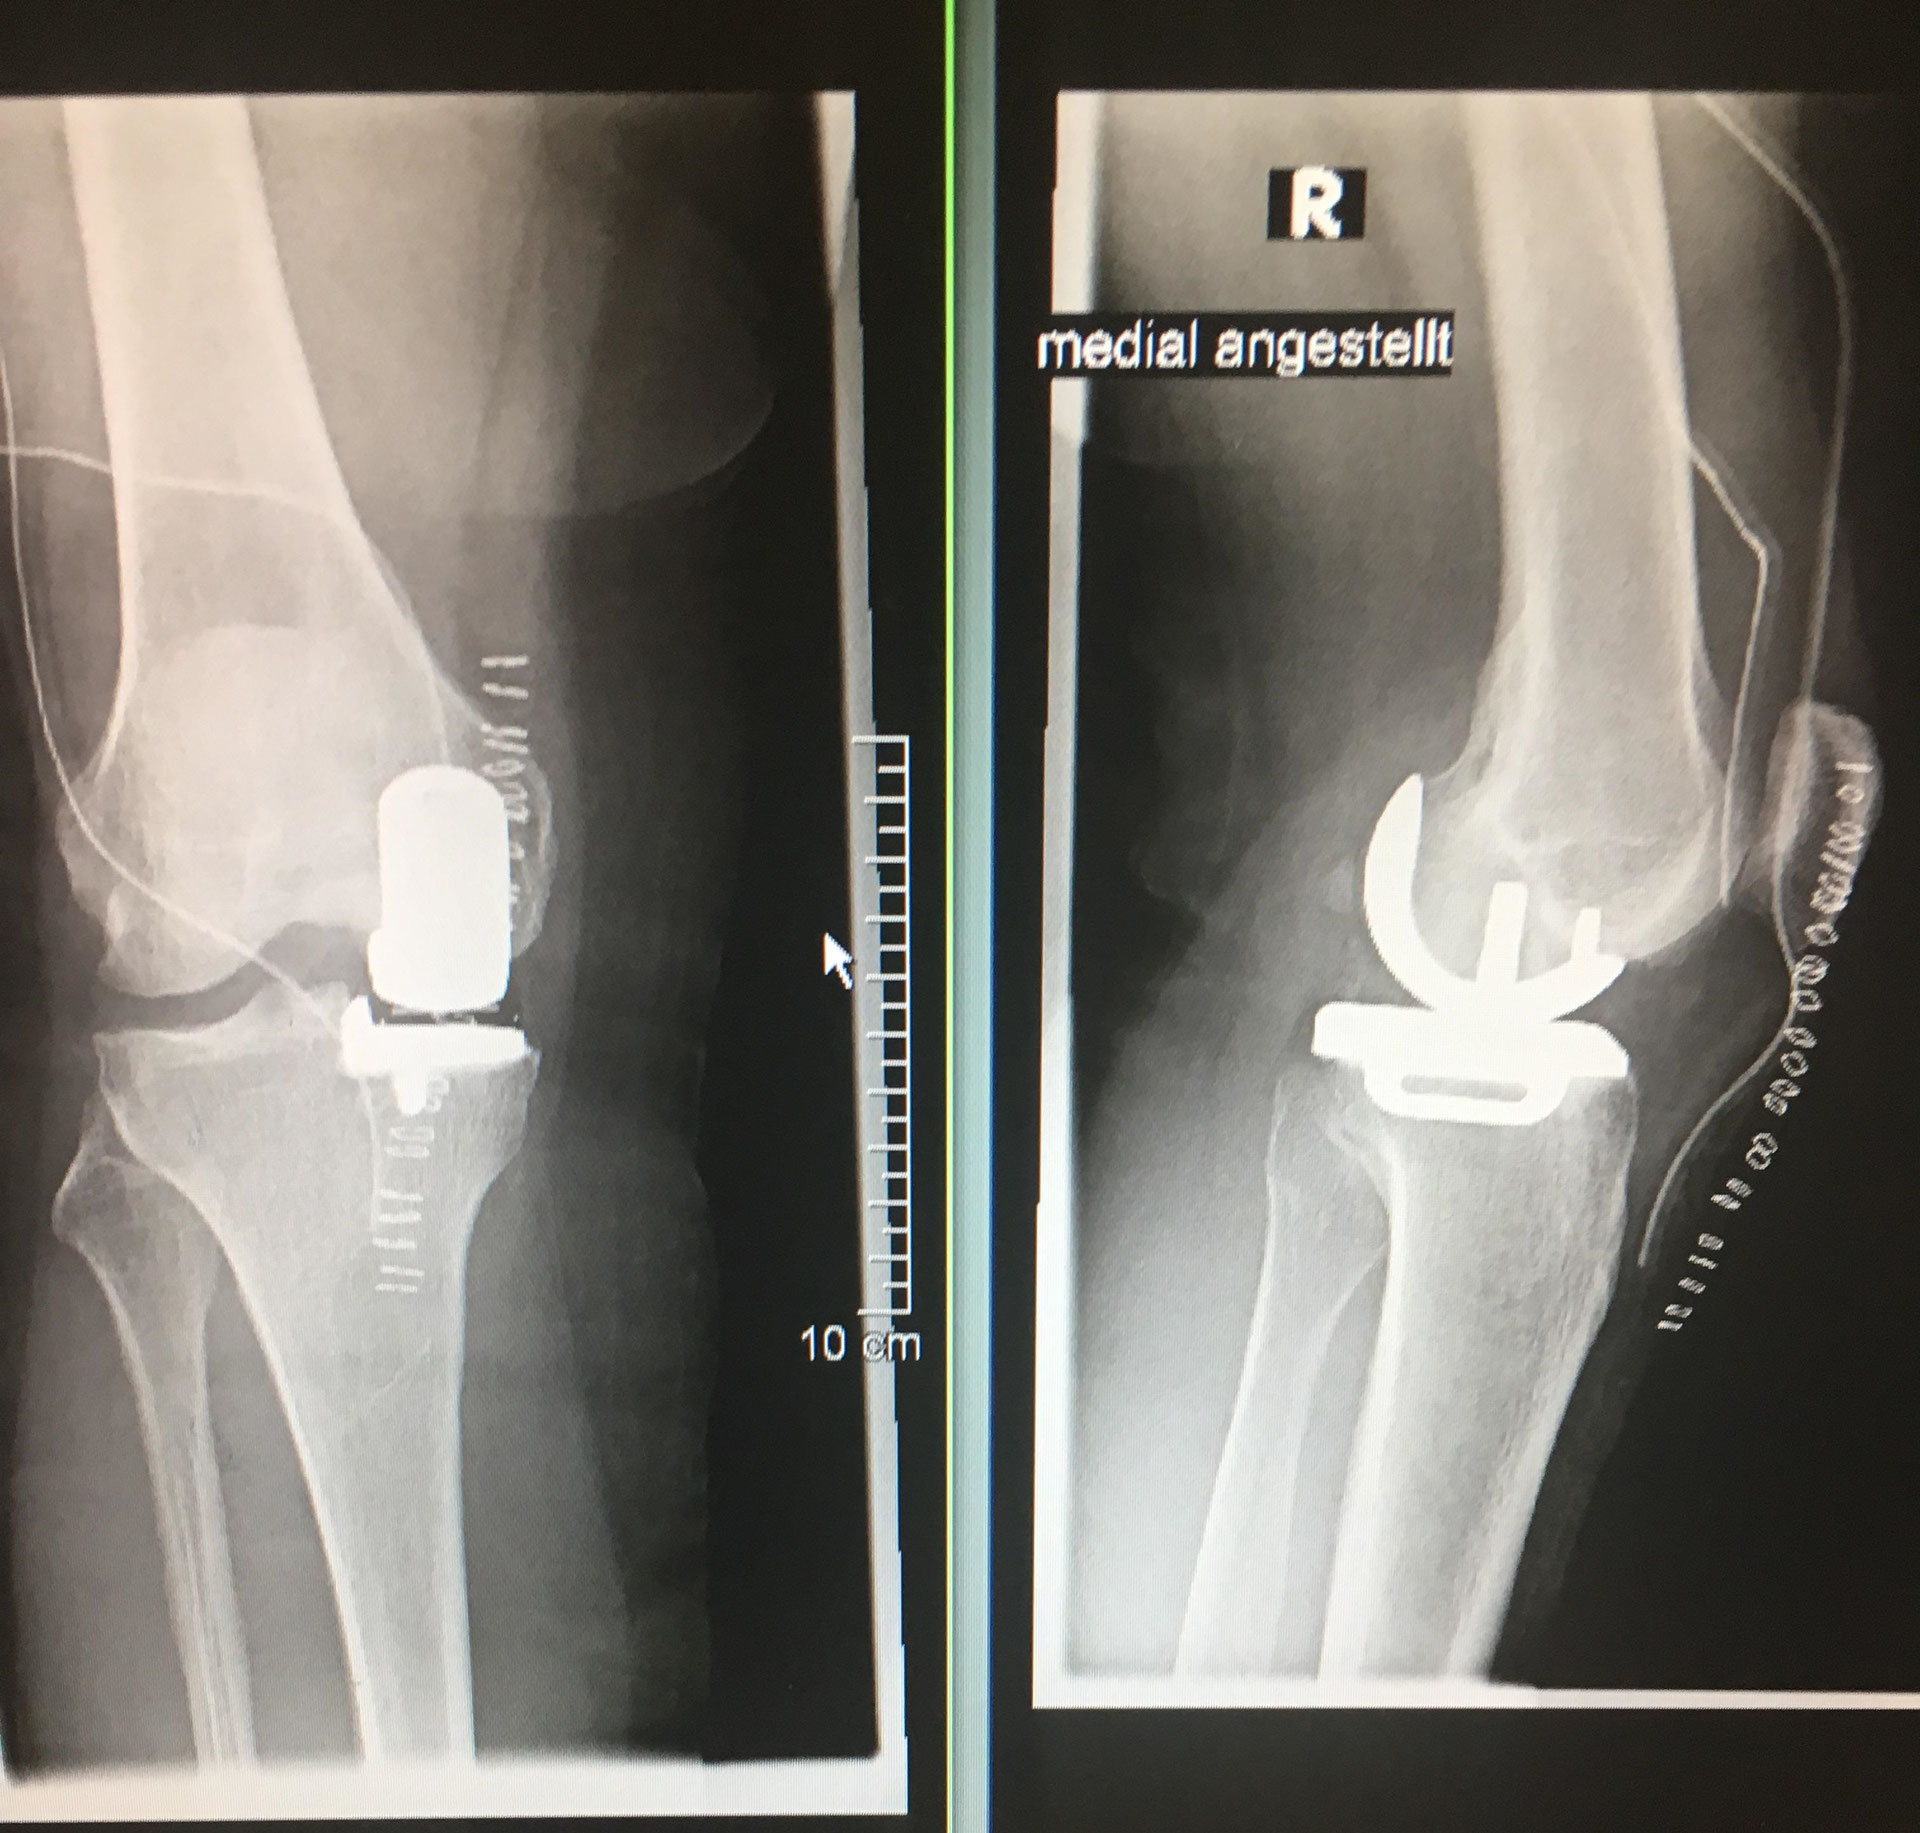

000 Patienten nach einer Knie-Operation an .Mit einer Arthrofibrose ist das Kniegelenk häufig geschwollen und gerötet. Briden treten beispielsweise im Kniegelenk als Folge einer Entzündung der Gelenkschleimhaut ( Synovitis) oder einer Schleimbeutelentzündung ( Bursitis) auf.Arthrofibrosen nach Knie-Endoprothetik können nach Implantation von Endoprothesen am Kniegelenk entstehen. Histologisch zeigt sich typischerweise eine subsynoviale Fibrose . Unter Arthrofibrose verstehen Mediziner die überschüssige Bildung von Bindegewebe im Kniegelenk. Ich scheine nach meiner Knie Tep im November 2013 eine Arthrofibrose zu haben. Die Arthrofibrose nach der Implantation einer Knie-Totalendoprothese gehört mit 1–13 % zu den häufigsten Komplikationen nach diesem Eingriff und ist somit für die relativ hohe Unzufriedenheitsrate der mit einer Knie-Endoprothese versorgten Patienten mitverantwortlich.Der Innsbrucker Facharzt für Orthopädie und Unfallchirurgie ist Experte für Arthrofibrose und schmerzhafte Knieprothesen. Erfahren Sie hier mehr, über den Aufbau und die Funktion des Kniegelenkes. Ergebnisse einer konservativen Behandlung der Arthrofibrose nach Knie-Endoprothetik (Poster) 7. Im Rahmen einer Erstuntersuchung, für die Jens nach Tirol reist, diagnostiziert Dr. Zusätzlich Propranolol 10 mg 1/0/0 über 40 Tage zur .Rehakliniken für Kniepatienten. In ausgeprägten Fällen muss ein erneuter operativer Eingriff durchgeführt .ich hatte eine Knie-Op, dadurch ist eine sog. Die primäre ist durch eine generalisierte Narbenbildung im Kniegelenk . Endoprothetik . Trotz relativ seltener Thematisierung ist die Arthrofibrose eine häufige Komplikation unter anderem nach Knie-TEP. nach und nach immer mehr beugen und strecken.Klinisch wird die Arthrofibrose nach Knietotalendoprothese (Knie-TEP) durch eine (schmerzhafte) Bewegungseinschränkung mit narbiger Bindegewebevermehrung definiert. Ursache der Beschwerden bei Arthrofibrose sind Wucherungen von Narbengewebe, die durch ein biochemisches Ungleichgewicht im . Das heißt, jedes Jahr erkranken weit über 40.Arthrofibrose: Zytokine, Stress und Thrombozyten (hypothetisches Krankheitsmodell) Annährung an eine mysteriöse Erkrankung nach Knie-Endoprothetik 8. Bei der erneuten Vorstellung empfiehlt der Operateur oft eine Narkosemobilisation, operative Entfernung des „Narbengewebes“ oder weitere intensive Physiotherapie.Da es sich eher um eine seltenere Erkrankung des Bewegungssystems handelt, ist es wichtig eine . Im ersten Teil meiner Arthrofibirose-Serie kannst du nachlesen, welche Therapien, mein Mann für die Behandlung der Arthrofibrose am Kniegelenk erhalten hat und welche zum Erfolg geführt haben.

Knieendoprothese (Knie-TEP): das künstliche Kniegelenk

Nach einem operativen Kreuzband ersatz kann sich durch Einklemmen (Impingement) bei der Kniestreckung kugelförmiges Narbengewebe am Transplantat bilden.Primäre Arthrofibrose nach Knie-Endoprothetik. Der Doc meint, für die .Offensichtlich aktiviert der Eiweißstoff dabei auch verschiedene molekulare Schalter, welche die Wundheilung fördern und dazu führen, dass im Gelenk eine Narbe entsteht. Narkosemobilisationen und arthroskopische bzw.